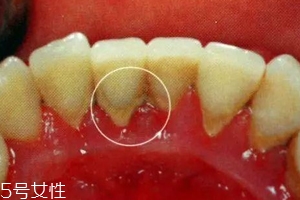

牙結(jié)石是不會(huì)自動(dòng)脫落的,因?yàn)樗卫蔚母街谘例X表面,當(dāng)然有時(shí)候會(huì)有極少數(shù)的牙結(jié)石會(huì)因?yàn)槟闼⒀阑蛘哂醚篮瀯兟洌皇菢O少數(shù)現(xiàn)象。所以有了牙結(jié)石千萬(wàn)不能忽視,它不會(huì)像感冒一樣會(huì)自行康復(fù)的,它們只會(huì)在你的牙齒表面沉積下來(lái),日積月累,使你的口腔患上炎癥,這樣只會(huì)導(dǎo)致牙齦炎癥逐漸加重,并發(fā)展為牙周炎,最終導(dǎo)致牙齒松動(dòng)脫落。不要奢求牙結(jié)石會(huì)自動(dòng)脫落了,請(qǐng)重視起來(lái),為了你有一口健康的好牙!

牙結(jié)石是由食物殘?jiān)?細(xì)菌+唾液長(zhǎng)期混合堆積而成,還是濃縮精華版,就像口腔內(nèi)有一小型垃圾場(chǎng),你說(shuō)能不臭嗎?牙結(jié)石的具體成分是「無(wú)機(jī)鹽」、「碳酸鈣」、「碳酸鎂」、「蛋白質(zhì)-多糖酶復(fù)合物」等。而且,這種堆積的牙結(jié)石會(huì)破壞牙齦乳頭和牙周組織,引起急性或慢性的牙周炎。在長(zhǎng)時(shí)間的腐蝕發(fā)酵下分解出一種酶,形成「二氧化碳」氣體,伴隨著口腔呼出的氣體一起呼出一種特殊的味道。所以不光是牙結(jié)石本身臭,它還會(huì)引起牙周疾病,口臭等。